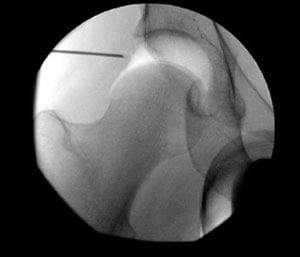

To perform the arthroscopy adequately, it is necessary to use traction to distract the joint under anesthesia. This distraction temporarily opens the space between the ball and socket by approximately one-half inch. This space is necessary to insert the scope and small instruments without damaging the labrum and cartilage. While this is possible under general anesthesia, we prefer epidural anesthesia, which provides muscle relaxation and complete pain relief but does not require a tube to be inserted in the airway, resulting in a much safer outcome. Fluoroscopy (X-ray) is used during the case to ensure that the instruments and scopes are inserted properly.

Traction creates space for instrument insertion